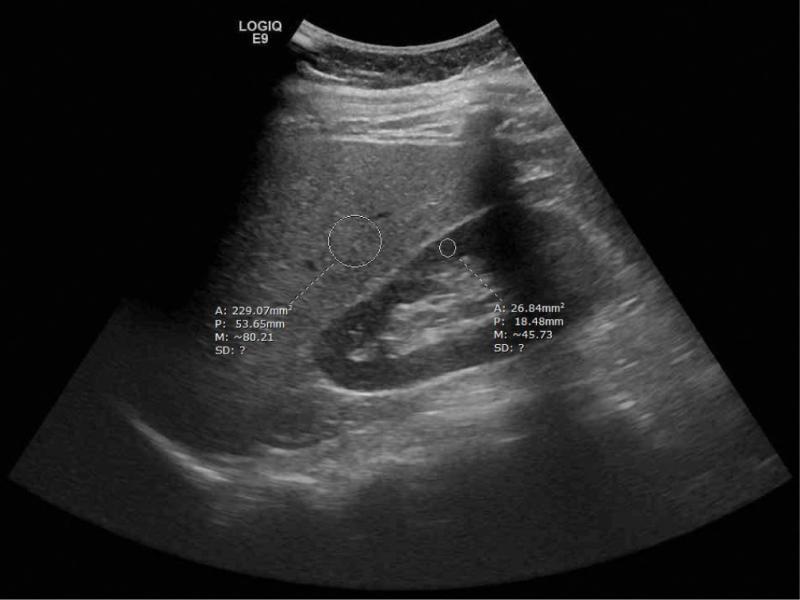

Fig. 1.